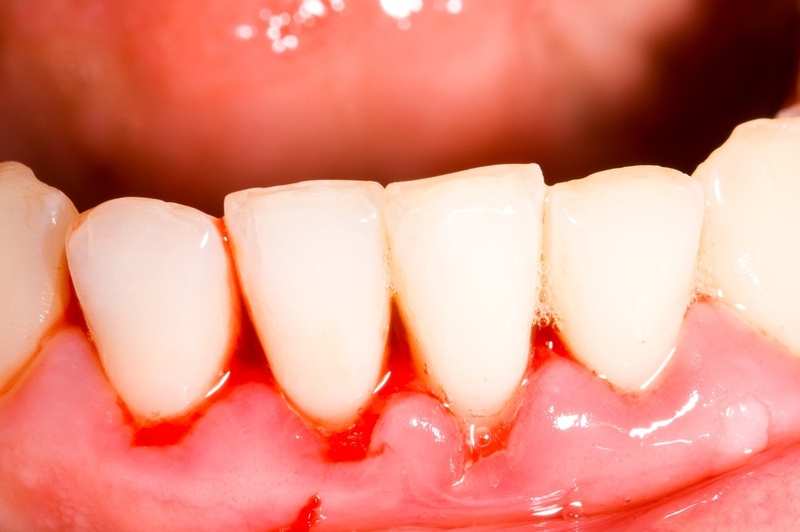

Nướu răng sưng đỏ và phồng lên, mất độ đàn hồi và nhạy cảm với nhiệt độ trong khoang miệng. Nếu đánh răng, dùng chỉ nha khoa hoặc khi ăn nhai thì có thể gây ra chảy máu. Đôi khi, chảy máu có thể xảy ra mà không có tác động gì. Việc nhận biết sớm các triệu chứng này có thể giúp phát hiện và điều trị sưng mộng răng kịp thời tránh tình trạng bệnh trầm trọng.